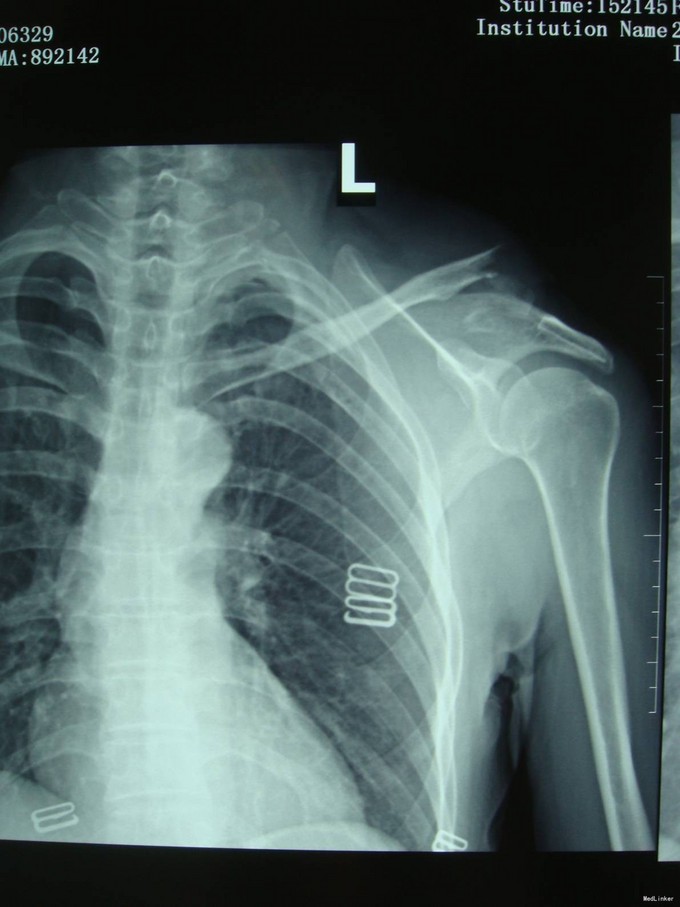

主诉:车祸外伤后9小时 患者自述2015-10-02车祸,导致左肩部受伤,疼痛,肿胀,肩关节活动受限,急送到苏家屯中心医院,诊断为“左锁骨骨折,气胸”,建议转院,为求进一步治疗来我院,诊断为“左锁骨骨折”,并收入我科,患者自受伤以来,无发热,呼吸略困难,无腹痛腹泻,饮食睡眠正常,大小便未见异常。

患者平车入病房,左肩部明显肿胀,压痛(+),骨擦音及骨擦感(+),左肩关节活动受限,左上肢感觉未见异常,左手指活动可,左手肌力5级,左桡动脉搏动可触及。